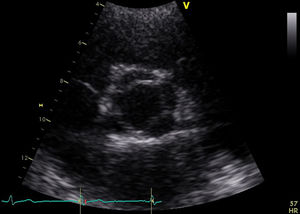

She was in sinus rhythm (∼80 bpm) with a diastolic murmur at the apex. The chest X-ray was normal with preserved cardiothoracic index. The preoperative echocardiogram revealed slightly enlarged left chambers (left atrium 46 mm; left ventricular systolic/diastolic diameters 41/59 mm; interventricular septal systolic/diastolic dimensions 11/15 mm, respectively) and preserved contractility (ejection fraction 63%). The aortic valve had four leaflets with preserved opening (no transvalvular gradient was present) but poor coaptation causing severe aortic regurgitation (vena contracta 8 mm) (Figure 1 and Video 1). The ascending aorta measured 36 mm.